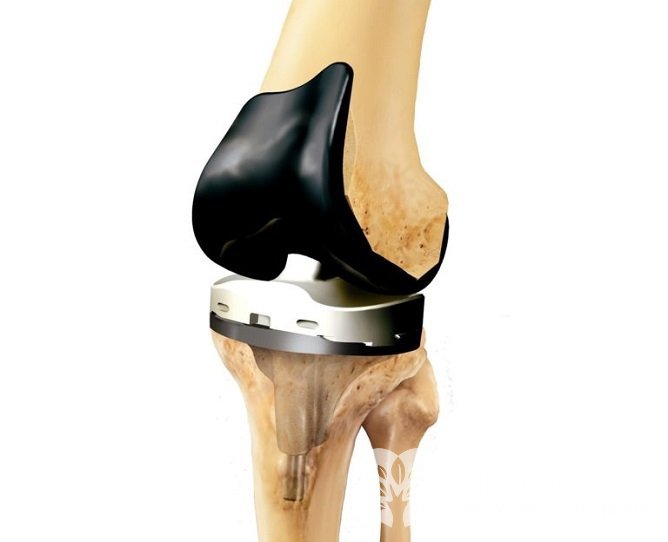

При неэффективности перечисленных методов воздействия, при наличии осложнений прибегают к оперативному лечению артрита коленного сустава:

Эндопротезирование коленного сустава позволяет устранить артритНа ранних стадиях заболевания применяют механический, лазерный или холодноплазменный дебридмент (сглаживание поверхности поврежденного хряща, удаление нежизнеспособных участков). Данный метод эффективно купирует болевой синдром, но носит временный эффект – 2-3 года.